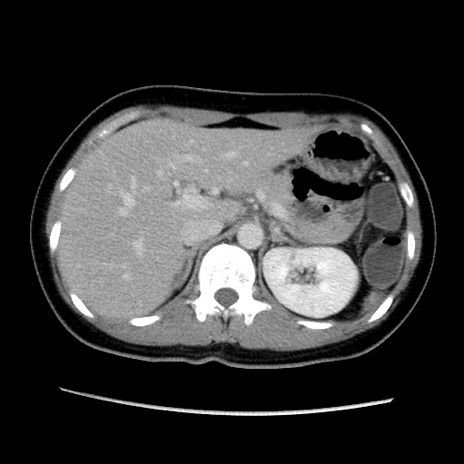

MRI(4日後)

【症例】40歳代女性

【主訴】上下腹部痛

【現病歴】2日目から下腹部痛あり。夜間は痛みで眠れなかった。昨日より上腹部痛と下痢が出現。臥位で痛みは軽快したため、休んでいた。本日になって臥位でも立位でも痛みが強くなってきたため救急要請。

【既往歴】子宮内膜症

【身体所見】部:平坦・軟、左上下腹部に圧痛あり、反跳痛あり。

【データ】WBC 21800、CRP 26.78